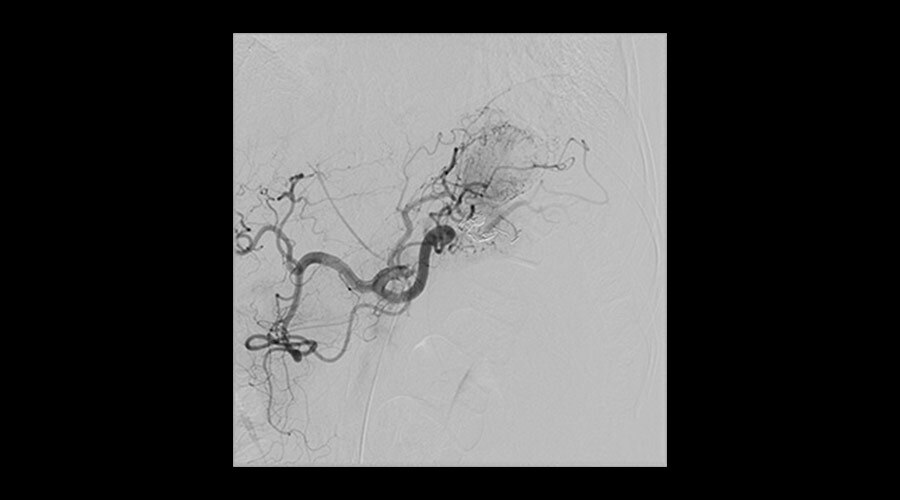

Klinik Görüntüler

-

Elde AVM